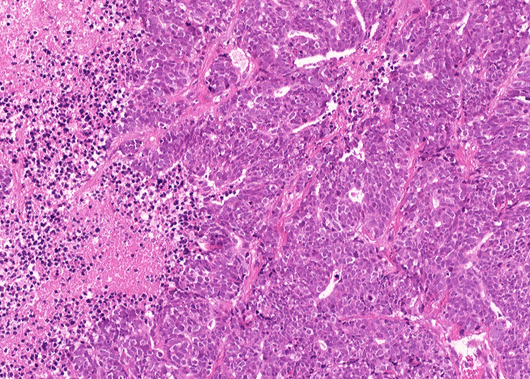

Cancer Sub-type: NSCLC Other: Large cell neuroendocrine carcinoma

- Cancer subtype: NSCLC Other: Large cell neuroendocrine carcinoma

- Application: Whole-exome sequencing, Hematoxylin and eosin staining, Immunohistochemistry